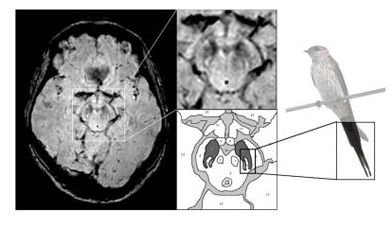

CHICAGO - Diffuse tensor imaging may help clinicians differentiate between mild traumatic brain injuries and post-traumatic stress disorder.

Diffusion tensor imaging has detected that alterations in brain connections among patients with temporal lobe epilepsy are more widespread than thought.